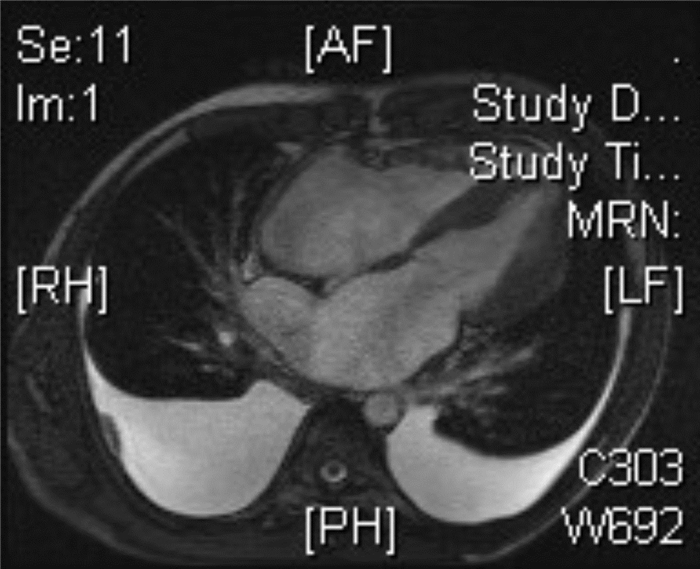

男,32岁,因间断胸闷、气短3年,加重2周入院。3年来患者因胸闷、气短多次就诊于外院,诊断为限制型心肌病。近2周上述症状加重,偶有端坐位呼吸及夜间阵发性呼吸困难,伴腹胀、食欲减退及少尿。既往吸烟史约20年,平均3-4支/d,已戒烟。否认高血压、糖尿病史、相关家族遗传病病史及寄生虫感染病史。入院查体:血压120/80 mmHg,端坐位,口唇发绀,颈静脉怒张,颈静脉搏动明显。双肺呼吸音粗,双下肺可闻及少量湿啰音。心界扩大,心率108次/min,律不齐,可闻及舒张晚期奔马律。肝肋下5 cm,双下肢中度凹陷性水肿。胸部CT示双心房增大,双肺散在炎症,双侧少量胸腔积液。心电图示(图 1)心房扑动,2:1-4:1传导,V1-V5导联T波倒置。肝、肾功能,血糖、心肌酶学、甲功八项未见异常。NT-pro BNP:6 110 pg/ mL(正常 < 100 pg/mL)。经胸心脏彩超示(图 2):左房(57.1 mm ×46 mm ×65.0 mm)、右房(47.3 mm×63.9 mm)增大;右室大小17.7 mm、左室大小32.7 mm;右室前壁厚度8 mm、室间隔17.7 mm、左室后壁13.3 mm;EF 62.4%;静息状态下左室壁收缩运动协调、运动幅度正常、心尖部收缩期近闭塞、左室流出道流速不快,E/A= 3.7,心内膜无明显增厚及回声增强,三尖瓣中度返流,二尖瓣轻度返流,心包少量积液。入院诊断为非梗阻性肥厚型心肌病舒张性心衰心律失常-心房扑动心功能Ⅳ级。经积极减轻心脏负荷、抗心律失常、抗感染、抗凝等对症治疗20 d,患者无明显呼吸困难,可平卧,双下肢无水肿。心脏MRI(图 3)结果示:双房增大,左、右心室壁及室间隔明显增厚、心室收缩功能正常,舒张功能受限;心脏灌注分析示心肌、心内膜未见延迟强化,支持上述诊断。出院后继续给予β受体阻滞剂、钙通道阻滞剂、抗凝及利尿治疗,随访中。

| 心肌及心内膜无延迟强化表现 图 3 患者心脏MRI |

该患者心脏彩超、心脏MRI表现为双心室、室间隔肥厚,心室腔大小及EF值正常,E/A=3.7及双心房扩大,符合HCM的影像学表现,具备了严重左右心室舒张功能受损,引起体肺循环淤血的病理生理基础;同时排除高血压、主动脉狭窄性疾病、糖尿病、甲状腺功能减退症等引起心肌肥厚的原因,故可诊断为非梗阻性肥厚型心肌病并舒张性心衰,临床极为少见。

限制型心肌病可有两种表型[6],最常见的是心内膜及心内膜下纤维化,心脏彩超表现心房明显扩大、心室壁轻度增厚、心室腔缩小、心尖部可呈闭塞状、心室舒张功能受损,心室肌收缩功能正常或轻度减低[3],心内膜增厚回声增强;心脏MRI除具备上述表现外,还可见心内膜呈条带状的延迟强化[7]。限制型心肌病的另一种少见表型是特发性限制型心肌病,以心肌间质纤维化为主,心内膜或心肌并无浸润或增厚,心脏彩超、MRI较易与肥厚心肌病鉴别。结合该患者虽然有双房扩大、心室腔大小正常、射血分数正常及心室舒张功能受损等影像学表现,心脏彩超及MRI同时提示心室壁、室间隔明显增厚且无心内膜特征性病变表现;同时治疗效果较好,因此排除限制型心肌病可能。